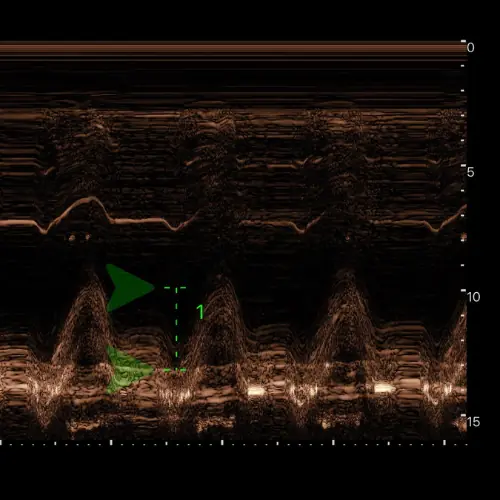

Fonction diastolique et précharge

Le remplissage, ou l’art de savoir quand s’arrêter